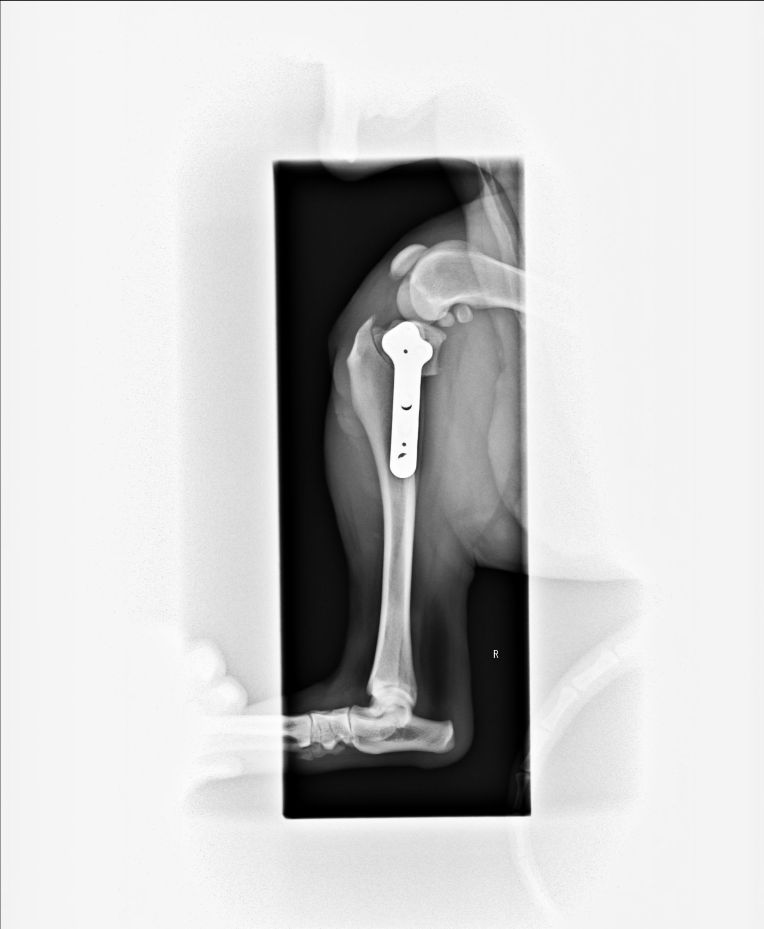

脛骨の先端を、専用のノコギリで切断しようとしてるとこですかね・・・。

多分こちらは切断した部分に角度をつけて、プレートで固定してるとこ。

手術後のレントゲンで、きちんとプレートが付いている事も確認。